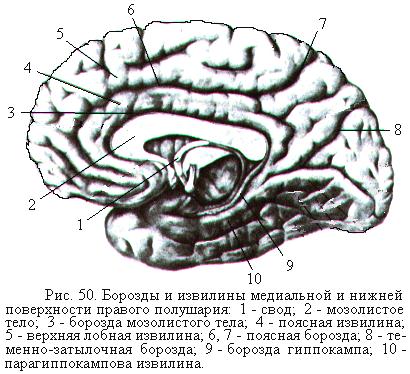

Анатомические снимки верхнелатеральной поверхности головного мозга